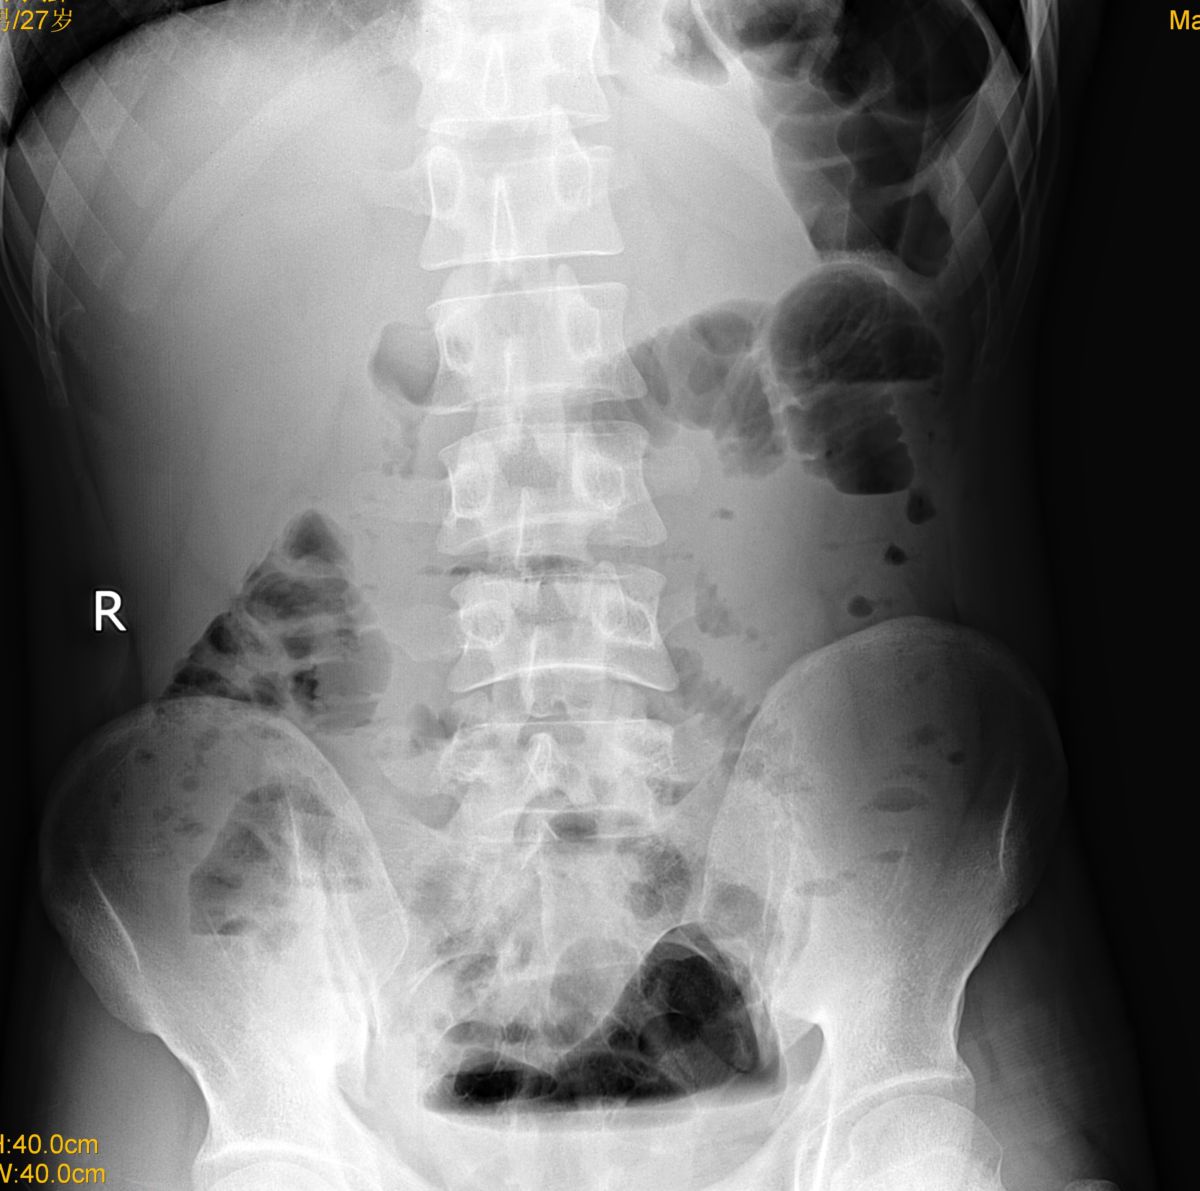

标题: X7881:腹痛、腹泻 [打印本页]

小肠低位不全性梗阻

盆腔内液气平靠得住吗?梗阻?

描写所见,建议结合临床。见液平的原因很多,梗阻只是其中一个原因,周围脏器炎症受累、急性腹痛应激反应、腹泻等等都可以。

小肠低位不全性梗阻。

考虑:小肠低位不全性梗阻。

随诊复查。